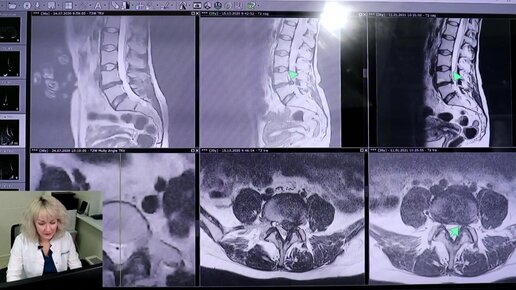

Спасаем спину от операции. Пациент рассказал, как проходит лечение методом резорбции